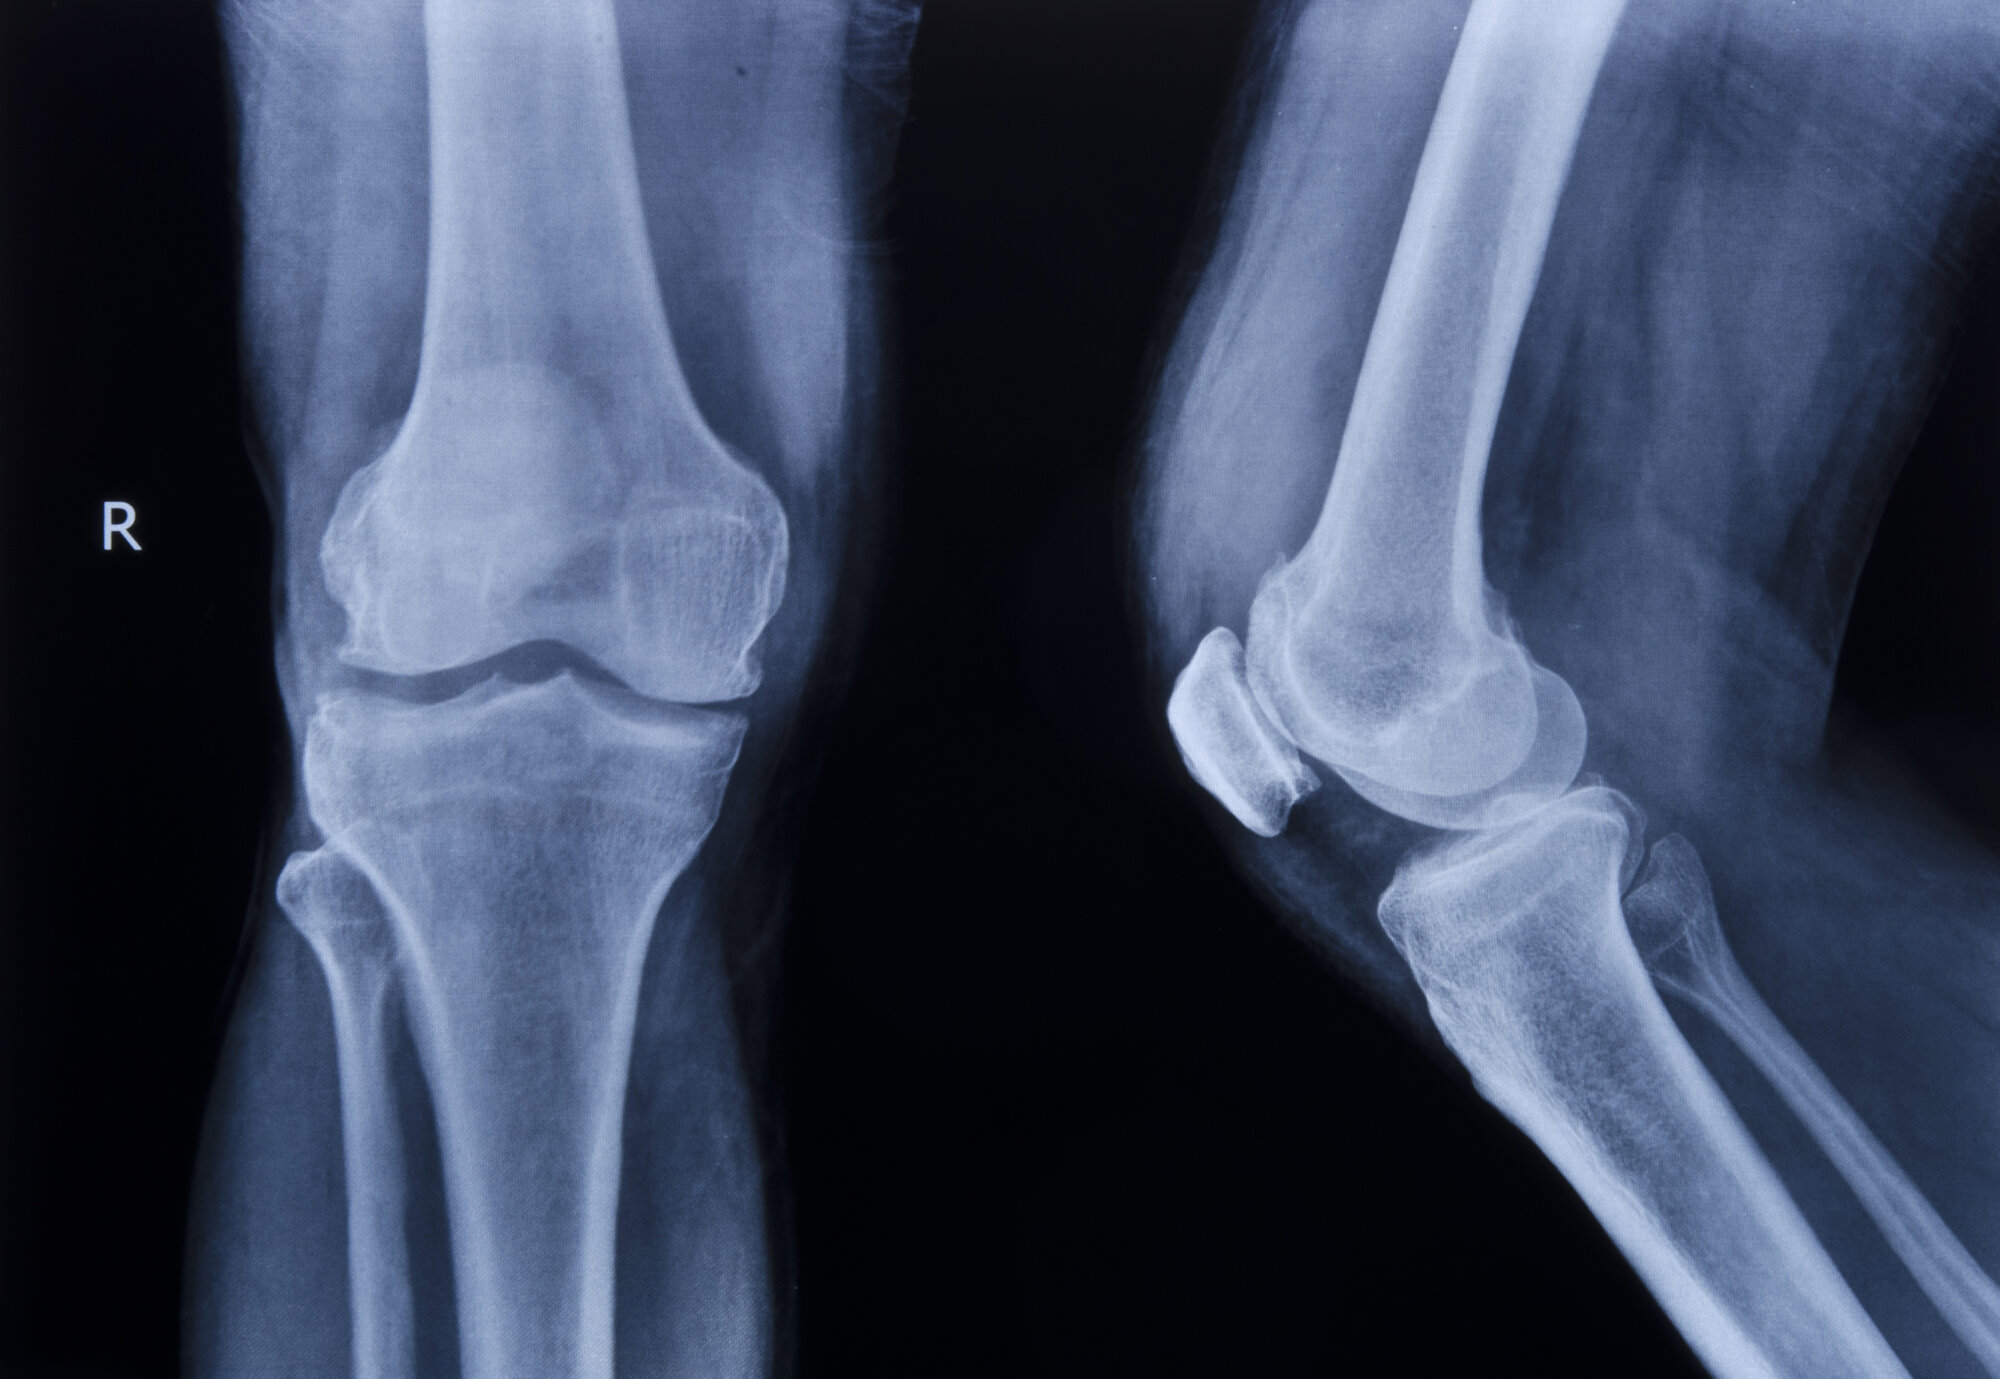

Etter det har helsestellet gjennomfotografert knea mine fleire

gonger, i takt med teknologiutviklinga. Men kvar gong har eg

Det enda opp med ny fotosession. «Hovudproblemet ditt er framleis

venstrekneet. Det er bein mot bein. No er du kanskje klar», lurte

lækjaren.